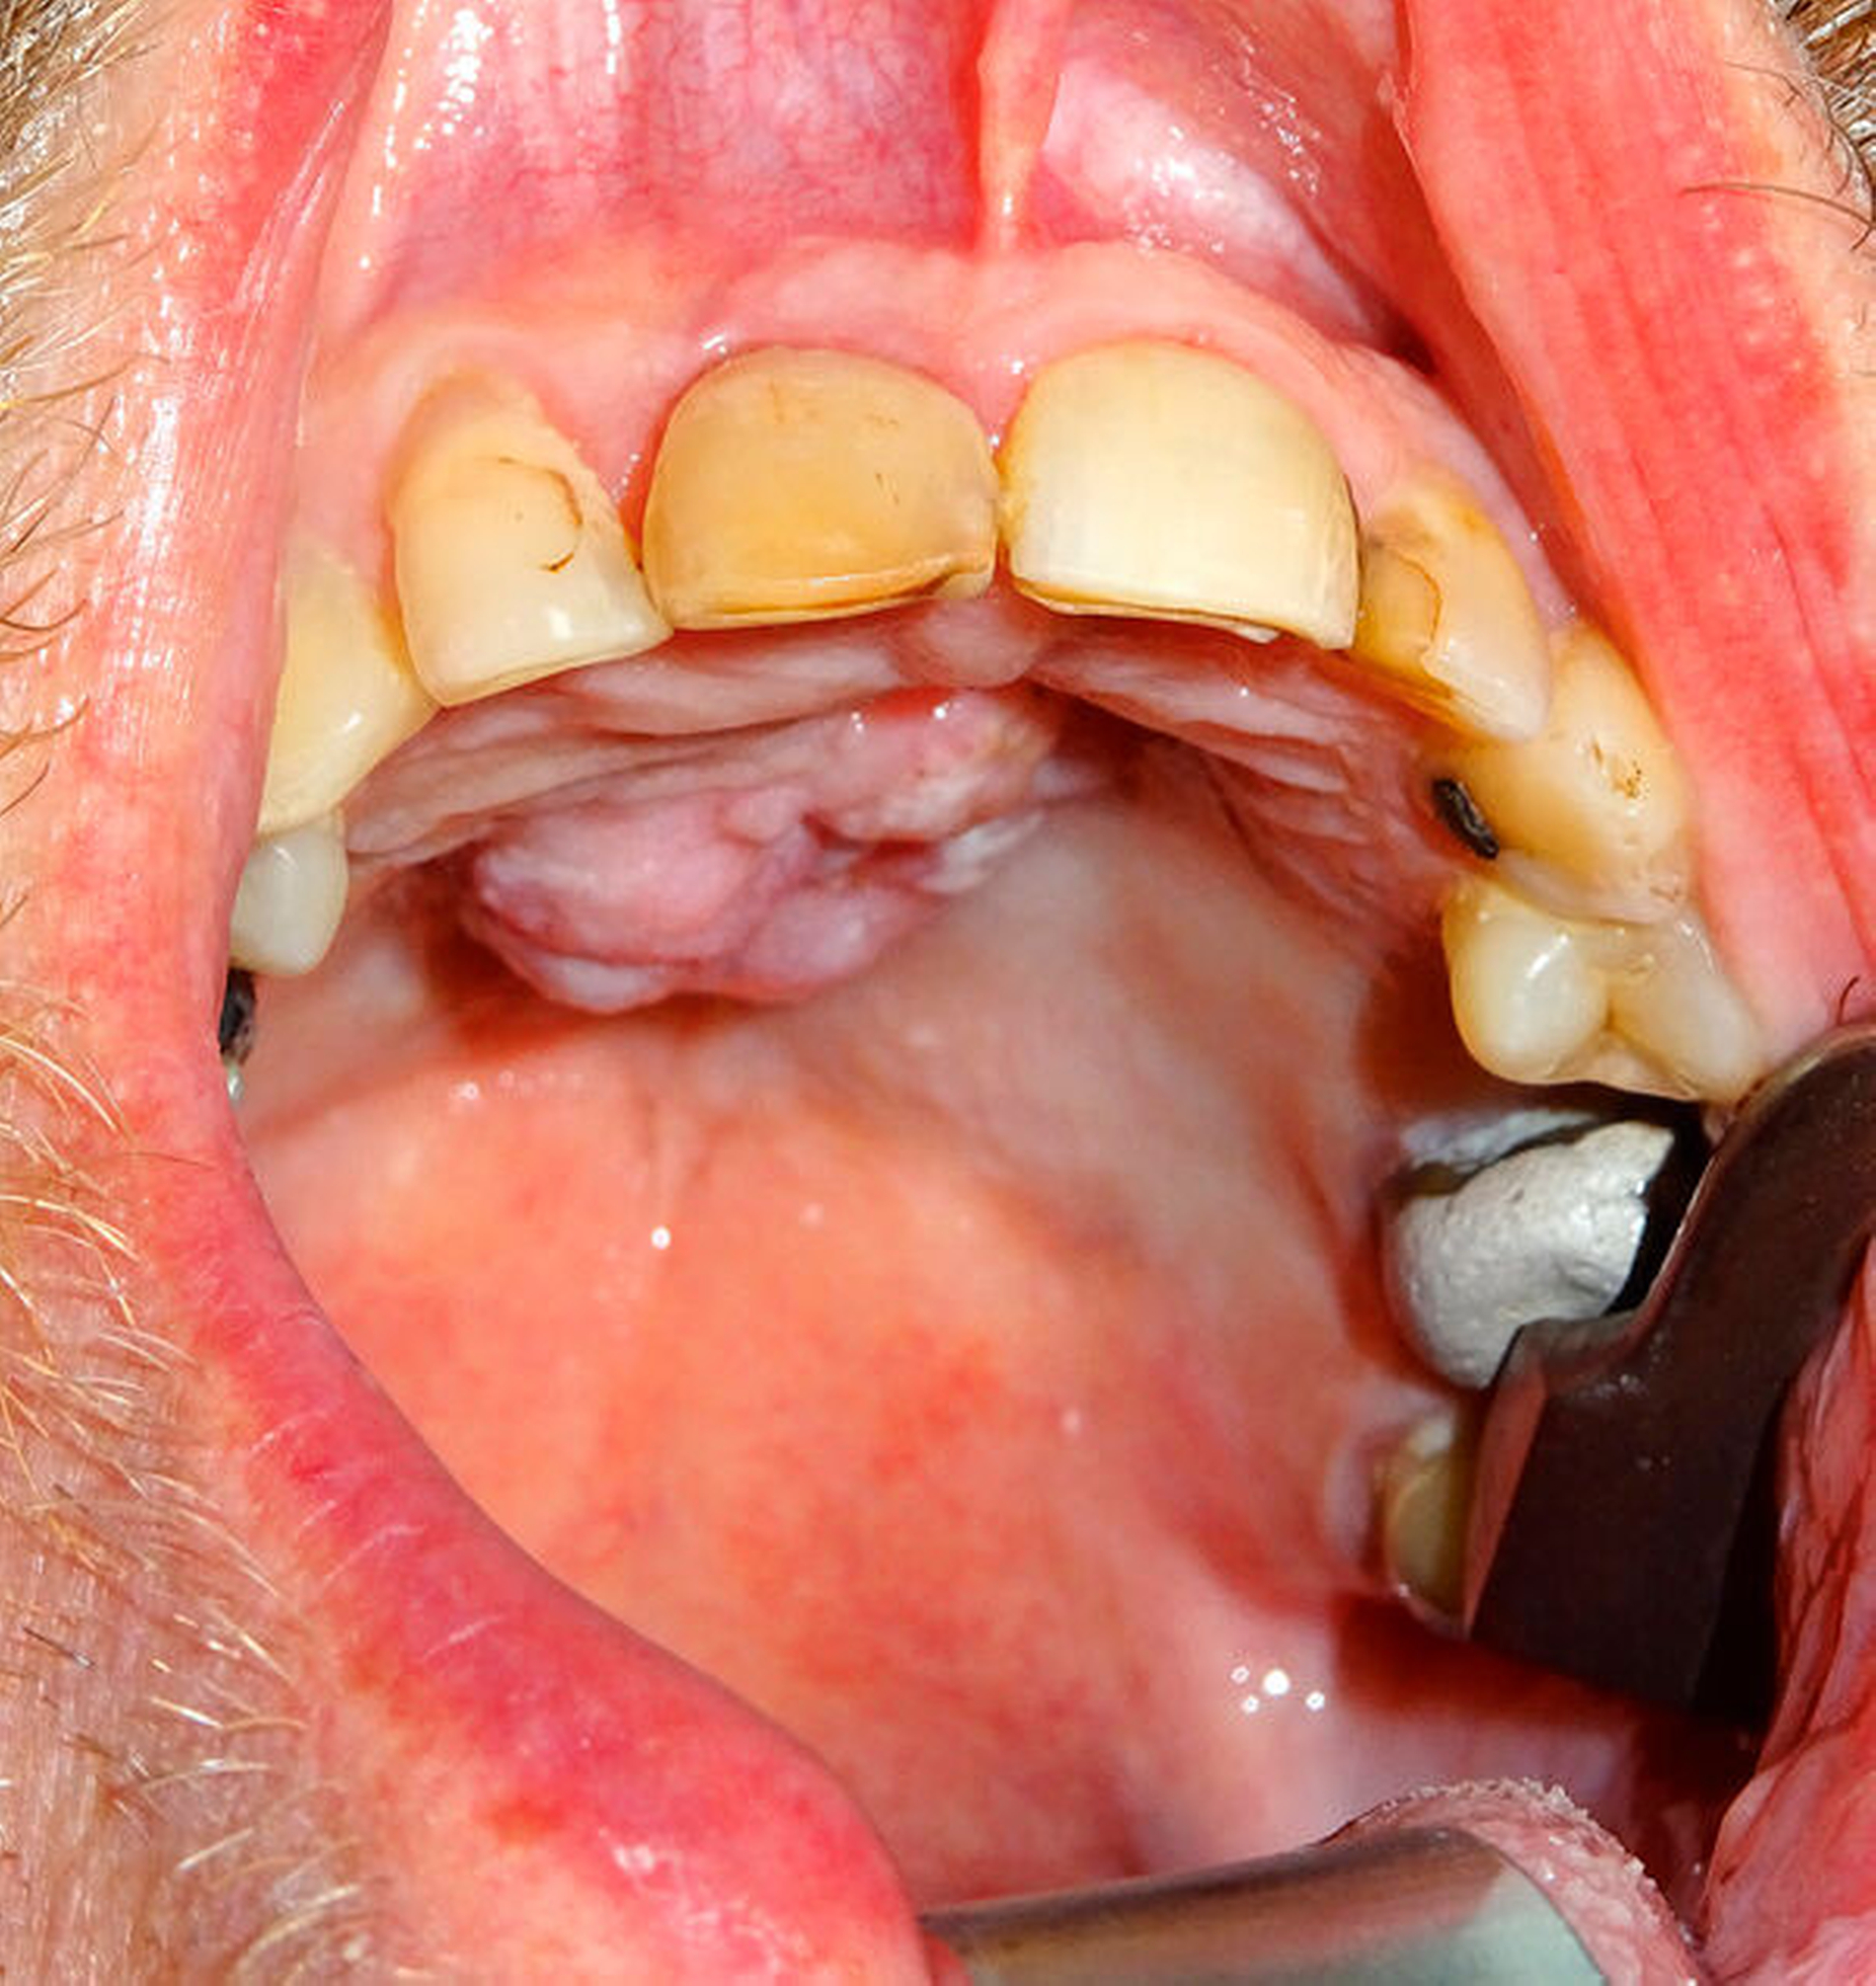

Dieser Fall zeigt, dass ein Tätowierung-erhaltendes Vorgehen nicht immer möglich ist. Ein 65-jähriger Patient mit großflächigen Tätowierungen am ganzen Körper stellte sich mit einem Plattenepithelkarzinom im Bereich des Alveolarfortsatzes des anterioren Oberkiefers und des Gaumens vor (Abbildung 2a). Zur Rekonstruktion nach Tumorentfernung war die Hebung eines Radialislappens geplant. Eine medizinisch sinnvolle Alternative bestand hierzu nicht. Nach sorgfältiger Abwägung und Aufklärung des Patienten erfolgte dann die Entscheidung für einen Radialislappen von links und die damit verbundene partielle Entfernung eines eintätowierten „Bacardi“-Emblems (Abbildungen 2b und 2c). Postoperativ kam es allerdings zu einer ausgeprägten Wundheilungsstörung im Entnahmegebiet (Abbildung 2d), während das Transplantat komplikationslos einheilte (Abbildung 2e).